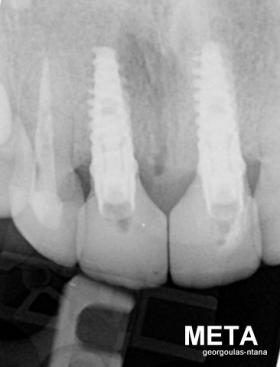

Στην ασθενή αυτή είχαν πραγματοποιηθεί 2 ενδοδοντικές θεραπείες (απονευρώσεις) που ακολουθήθηκαν από 2 ακρορριζεκτομές χωρίς επιτυχία. Η ασθενής ήταν δυσαρεστημένη με την όψη κ το χρώμα των δύο δοντιών και φυσικά με το πρόβλημα υγείας που δημιουργήθηκε. Πραγματοποιήθηκε εξαγωγή των δύο δοντιών, οστική αύξηση και τοποθέτηση 2 εμφυτευμάτων στις θέσεις των δύο κεντρικών τομέων. Τα δύο εμφυτεύματα αποκαταστάθηκαν με 2 υβριδικά κολοβώματα από διπυριτικό λίθιο και ολοκεραμικές στεφάνες ενώ στους 2 πλάγιους τομείς τοποθετήθηκαν επίσης ολοκεραμικές στεφάνες.